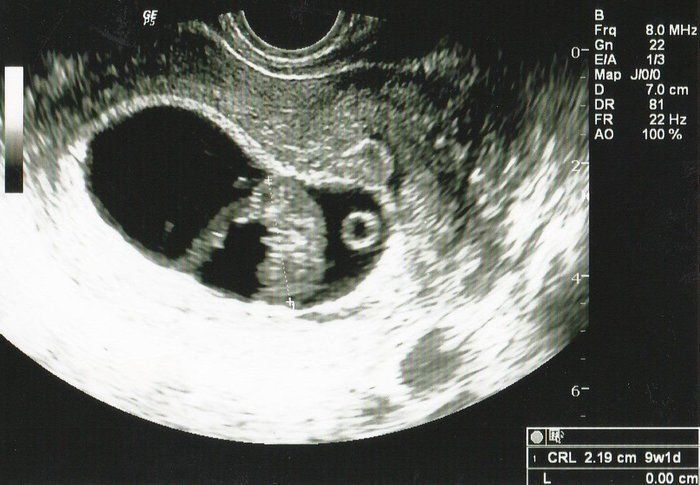

Tomomiさんの妊娠8週目のエコー写真 ついに産婦人科へ転院

妊娠3カ月目に突入し、初めての産婦人科へ。里帰りまでの約半年お世話になりました。

初めて心音を聞かせてもらい、震えるほど感動しました。「ドクドクざわざわ」、一生懸命生きている命の音を聞き、「ママもしっかりしなくちゃ」と背筋が伸びました。

母子手帳交付の許可も降り、4年目の結婚記念日に最高のプレゼントを貰いました。